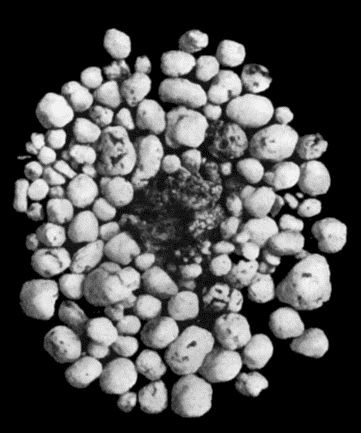

541 168.Multiple partially ossified Chondromas of Synovial Membrane from Shoulder-joint

542 169.Multiple Cartilaginous Loose Bodies from Knee-joint